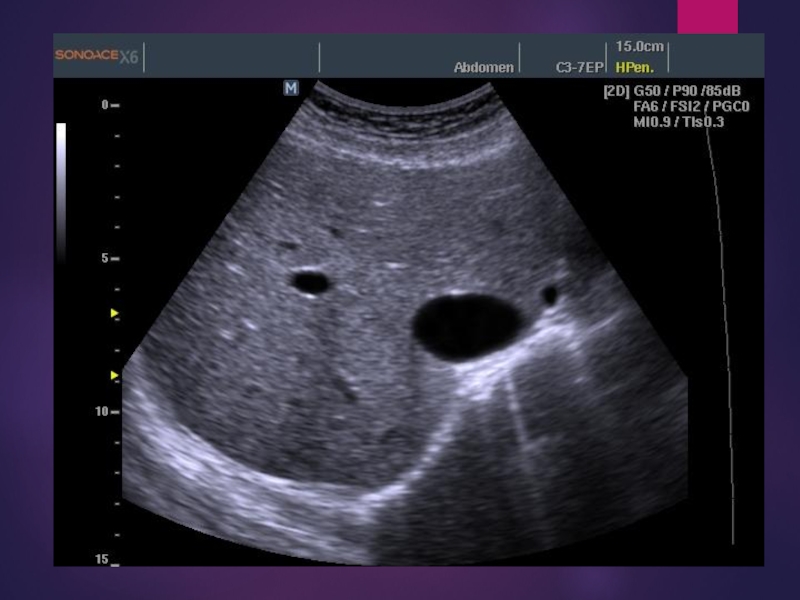

Слайд 12УЗИ желчного пузыря

исследуются аномалии развития пузыря и желчных протоков, диагностируется

желчекаменная болезнь, холециститы, полипы, доброкачественные и злокачественные опухоли.

УЗИ желчного пузыря исследуются аномалии развития пузыря и желчных протоков, диагностируется желчекаменная болезнь, холециститы, полипы, доброкачественные и злокачественные